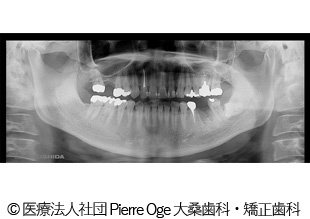

【症例1】左上456、右下6 インプラント治療

- 治療前

- 治療後

- 治療名

- 左上456、右下6 インプラント治療

- 費用

- 1,578,000円(税込)

- 費用の詳細

- 検査代:32,000円(税込)/手術代:759,000円(税込)/補綴代:787,000円(税込)

※当時の金額 - 期間

- 8ヵ月

- 通院回数

- 17回

- 性別・年齢

- 50代女性

治療内容

患者様の症状

噛むと痛い。歯根破折。インプラント治療希望でご来院されました。

治療方法

左上奥歯の歯根破折、欠損部に代わってインプラントを埋入。骨量が少なかったため同時に人工骨移植。その後、インプラントが安定してから被せ物を入れることで機能面・審美面の回復に繋がりました。

治療結果

歯根破折、欠損部を補うことができ、機能面・審美面の回復に繋がりました。

治療を行う上での注意点(リスク・副作用)

疼痛、腫脹、青アザ、出血、神経麻痺、鼻出血、補綴物の破損、インプラント体の破折、咬合違和感、インプラント周囲炎。